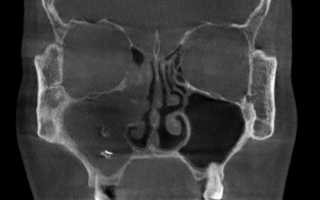

- КТ. Компьютерная томография считается в клинической отоларингической практике лучшим методом, применяемым для осмотра воздухоносных придаточных полостей и назальных лабиринтов.